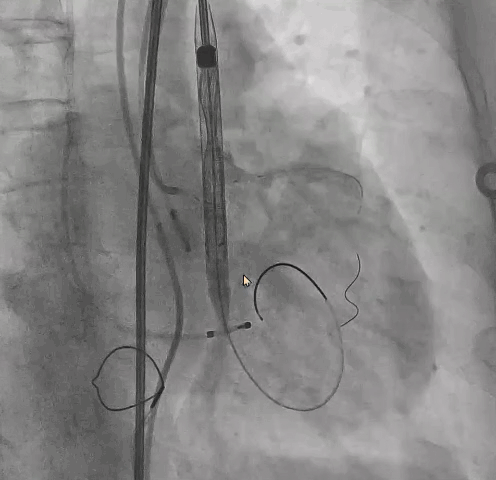

行左冠保护,预置左冠球囊

第一折:血压异常降低

降低原因 — 冠脉?

输送器系统跨瓣后,出现血压异常降低,血压下降至55/30mmHg,给予升压药物无效。

● 考虑冠脉保护球囊置入较深可能影响冠脉灌注?

冠脉造影评估灌注后撤出球囊,血压未回升,给予升压药物仍无法回复血压。

降低原因 — 二尖瓣?

● 考虑超硬导丝缠绕腱索导致二尖瓣关闭受限,予以超声检查。

术前评估主动脉瓣可见中大量反流,二尖瓣轻微反流。

术中超声可见超硬导丝缠绕,二尖瓣大量反流,引起血压无法回升。

撤出输送器,重新调整超硬导丝大小及位置,血压回升,患者情况稳定。